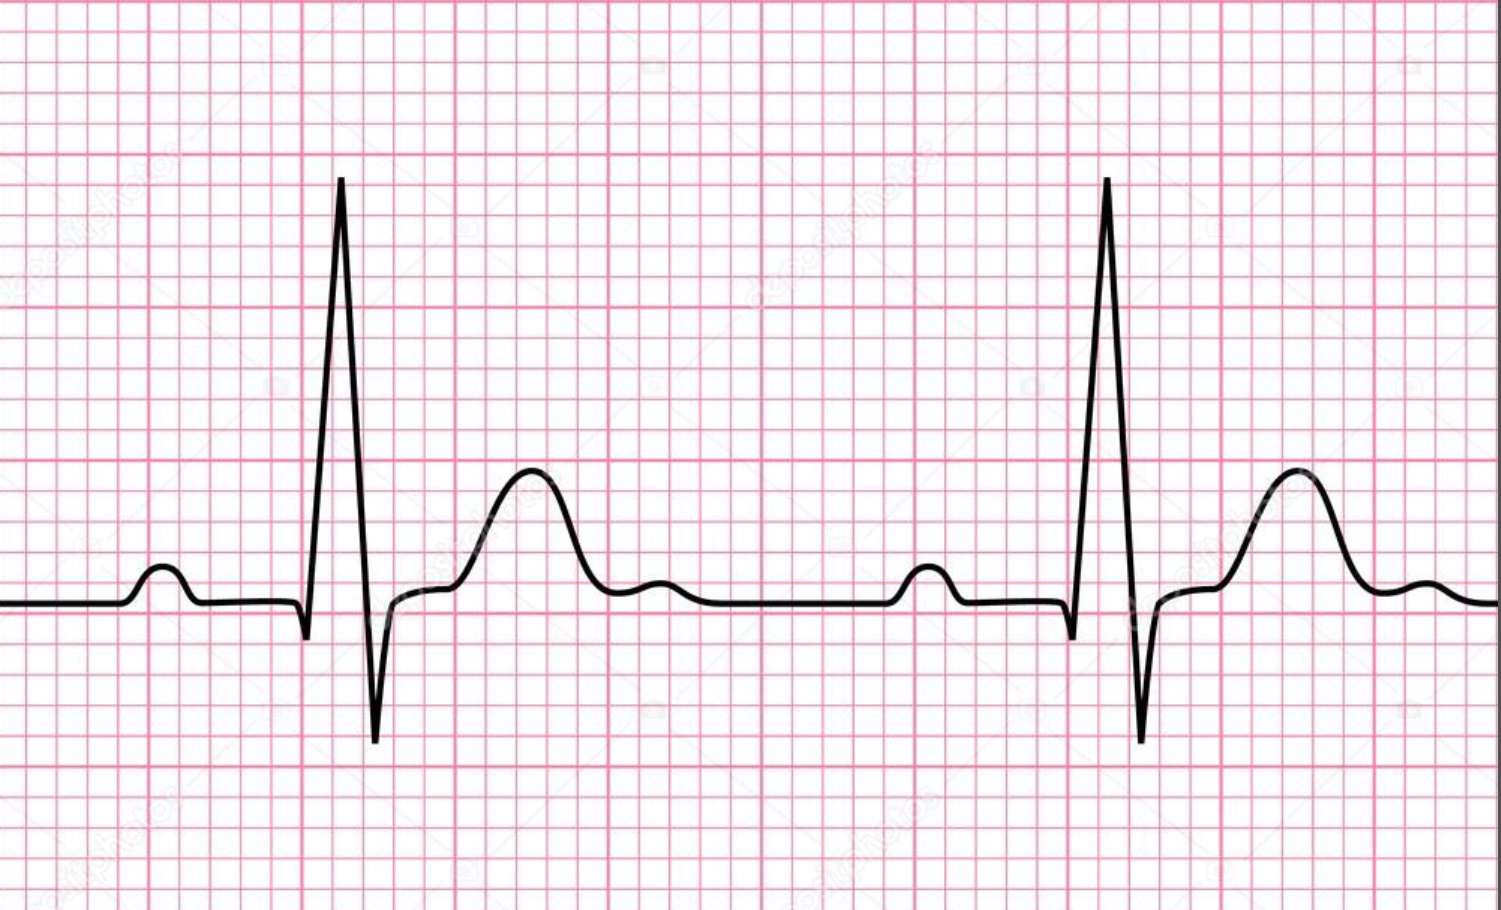

P wave

atrial depolarization

Precedes atrial contraction

QRS complex

ventricular depolarization

Precedes ventricular contraction

T wave

ventricular repolarization

PR interval

Name #1

QRS interval

Name #2

QT interval

Name #3

TP interval

Name #4